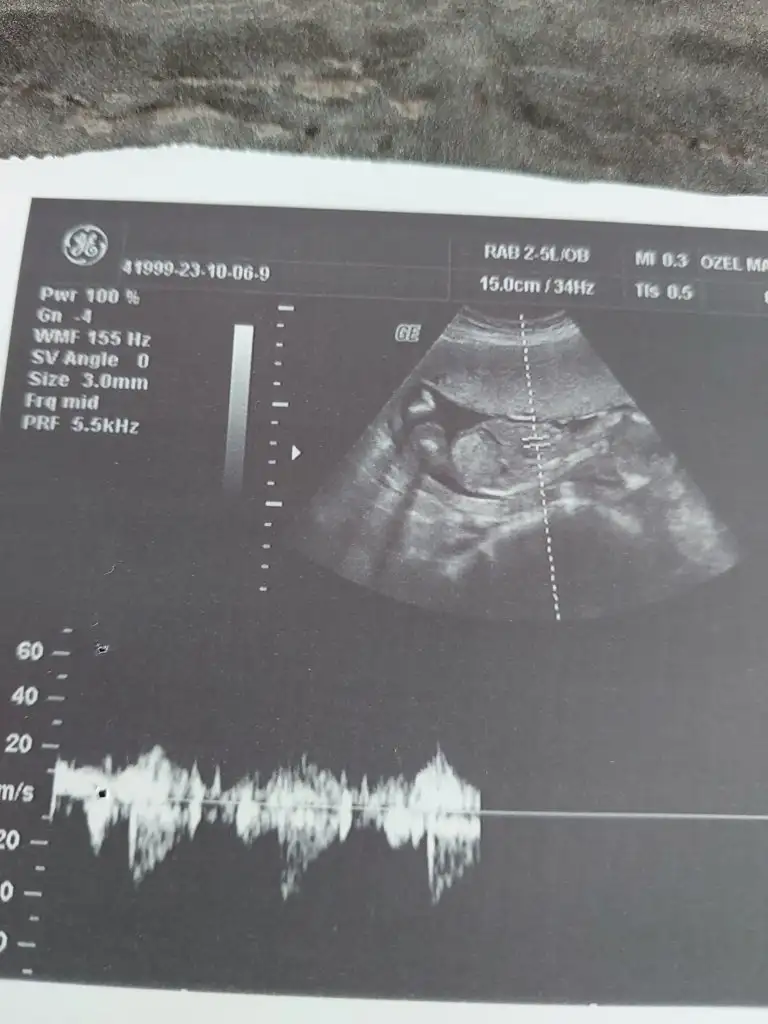

Merhaba arkadaşlar banada bakabilir misiniz? 12+3 kız dedi doktorum 17. erkek dedi. Yanılmış olabilir mi? Kız hissediyorum hep:) 12 ve 17 haftaya ait görüntüleri